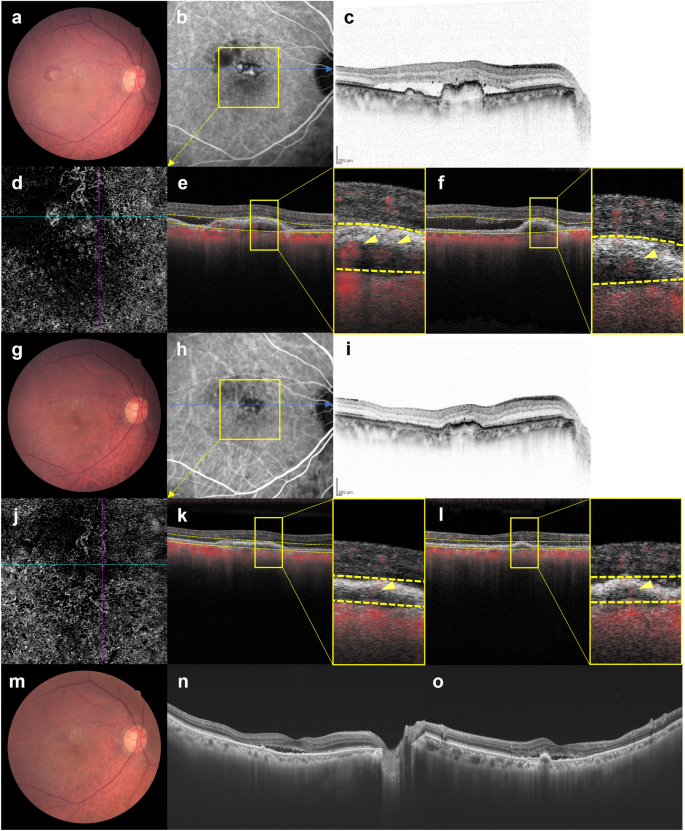

Images of the right eye of an 81-year-old man with polypoidal choroidal vasculopathy in the group showing persistence of blood flow signals within polypoidal lesions. (a–f) Baseline. Best corrected-visual acuity (BCVA) of the right eye is 0 logarithm of the minimal angle of resolution (logMAR) units. (a) Color fundus photograph shows a serous retinal detachment (SRD) and subretinal hemorrhage. (b) Indocyanine green angiography (ICGA) shows polypoidal lesions with a branching neovascular network (BVN) superior to the fovea. (c) Optical coherence tomography (OCT) B-scan image through the polypoidal lesions shows pigment epithelial detachments (PEDs) with SRD. (d) Optical coherence tomography angiography (OCTA) en face image shows blood flow signal corresponding to the polypoidal lesion and the BVN. (e, f) OCTA B-scan images (e: horizontal, f: vertical) show blood flow signals within the PED corresponding to the polypoidal lesions (arrowheads). (g–l) 3 months after the initial treatment. BCVA of the right eye is 0 logMAR units. (g) Color fundus photograph shows diminished subretinal hemorrhage without SRD. (h) ICGA shows persistent polypoidal lesions. (i) OCT B-scan image shows PED to be diminished without SRD. (j) OCTA en face image shows unclear blood flow signals within the polypoidal lesions. (k, l) OCTA B-scan images (k: horizontal, l: vertical) show blood flow signals within the PED corresponding to the polypoidal lesions (arrowheads). (m–o) One year after the initial treatment. BCVA of the right eye is 0 logMAR units. In total, 8 injections were required during the 1-year study period due to SRD recurrence. (m) Color fundus photograph shows no hemorrhage. (n, o) OCT B-scan images through the fovea (n: horizontal, o: vertical) show an SRD.